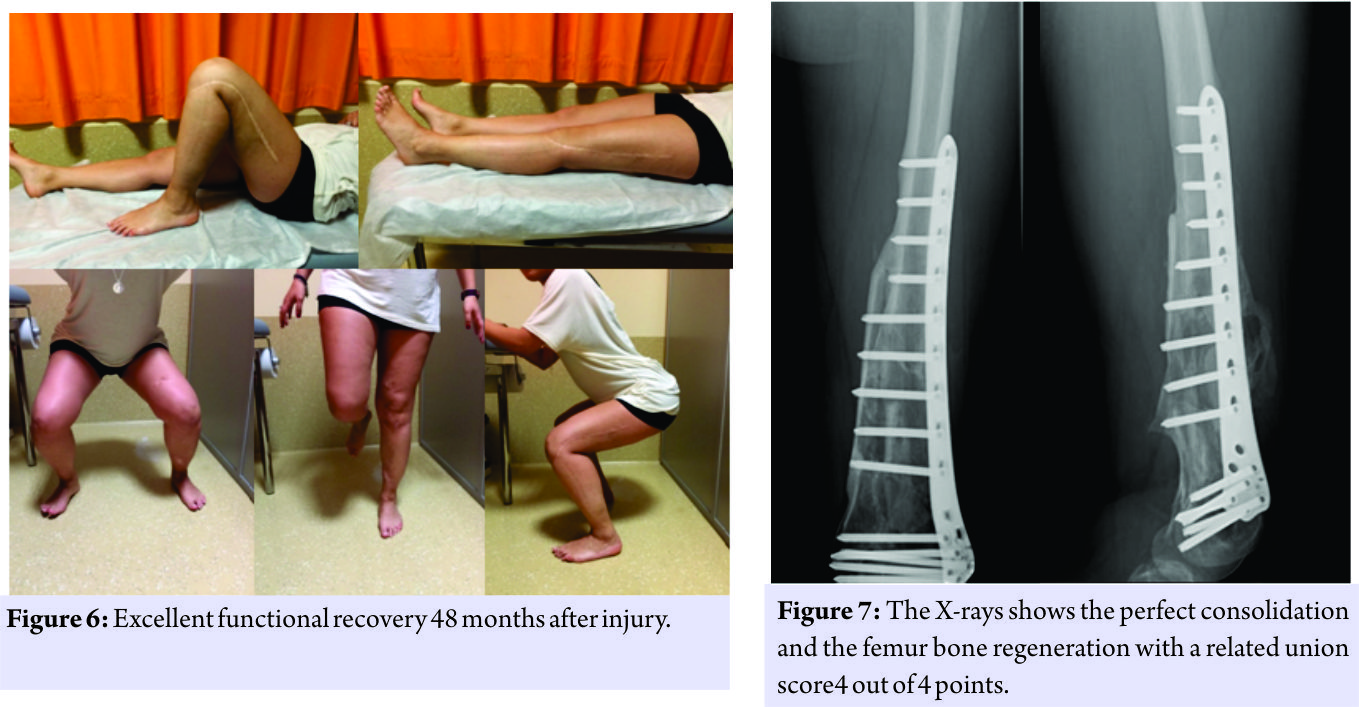

The patient was not treated surgically for the fissure of the spleen, and the resolution of the neurological picture took place after 6 days. The patient was submitted to a specific antibiotic therapy according to the protocol for the open fractures and was monitored with clinical and laboratory examinations. The 21stday post-trauma, without any clinical or laboratory signs, the patient was operated on with a less invasive stabilization system plate and screws, cortical and cancellous bone grafting allogeneic bank, and autologous stem cells taken from the iliac crest, PRP rich in leukocytes and replanting of native bone. The surgical access chosen was the lateral subvastus to preserve the perforating arteries(Fig.4). The patient was monitored with 15 days clinical follow-up, laboratory, and radiological at 1 month, 2 months, 3 months, 6 months, 12 months, 18 months, 24 months, 36 months, and 48 months. The indices used to evaluate the outcomes of this intervention were the knee injury and osteoarthritis outcome score (KOOS), the related union scorefemur (R.U.S.F.) for the femoral bone healing, and the score radiographic union score for tibial fractures (R.U.S.T.). For bone consolidation of shank, the short form 12 health survey (SF-12) for the quality of life, and the number of complications and re-operations. The patient in the immediate post-operative made active and passive mobilization of the knee until the 3rdmonth, reaching a flexion of 90°. The patient was subjected to the intervention of removal of the external fixator and intramedullary nailing of the tibia 3 months after the first surgery(Fig. 5). The patient has walked with a partial load up to 6 months after the injury and then began to progress to a total load. At 12 months, the patient had a KOOS of 89.3 points, a SF-36 of 89.3 points, the R.U.S.T. 3 out of 3 points, and R.U.S.F. 3 out of 4 points. At 24months, the patient had an intramedullary nail removal of 100 points KOOS, 100 points SF-36, the R.U.S.T. 3 out of 4 points, and R.U.S.F. 4 out of 4 points. At follow-up at the past 36 months, a year after the removal of plaque and nail, the patient showed KOOS 100 points, a SF-36 out of 100 points(Fig. 6), and R.U.S.T and R.U.S.T 4 out of 4 points(Fig. 7). After 2 years, the patient had the tibia nail removed. The patient did not present any complications throughout the post-operative and follow-up.

The patient has walked with a partial load up to 6 months after the injury and then began to progress to a total load. At 12 months, the patient had a KOOS of 89.3 points, a SF-36 of 89.3 points, the R.U.S.T. 3 out of 3 points, and R.U.S.F. 3 out of 4 points. At 24months, the patient had an intramedullary nail removal of 100 points KOOS, 100 points SF-36, the R.U.S.T. 3 out of 4 points, and R.U.S.F. 4 out of 4 points. At follow-up at the past 36 months, a year after the removal of plaque and nail, the patient showed KOOS 100 points, a SF-36 out of 100 points(Fig. 6), and R.U.S.T and R.U.S.T 4 out of 4 points(Fig. 7). After 2 years, the patient had the tibia nail removed. The patient did not present any complications throughout the post-operative and follow-up.